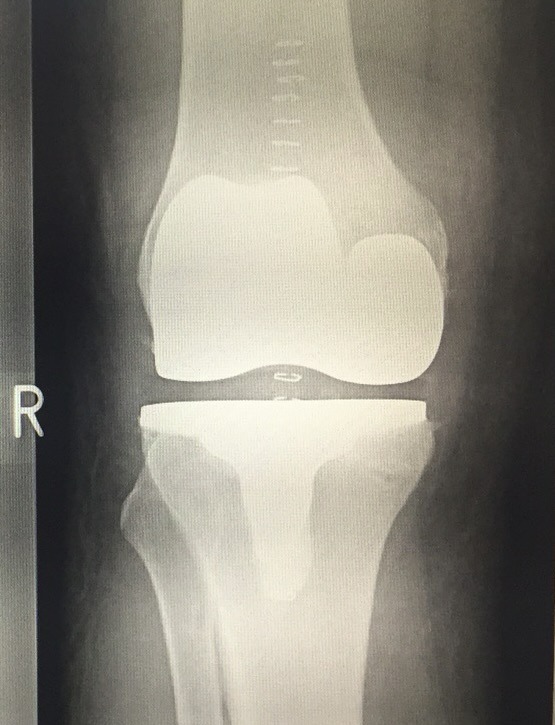

Η εξατομικευμένη αρθροπλαστική γόνατος είναι σύγχρονη τεχνική αντικατάστασης του γόνατος όπου ο σχεδιασμός (και συχνά τα εργαλεία και τα εμφυτεύματα) προσαρμόζονται αποκλειστικά στη δική σου ανατομία, με βάση MRI ή CT.

Πλεονεκτήματα

- Πιο φυσιολογική κίνηση του γόνατος

- Καλύτερη ισορροπία μαλακών μορίων

- Μείωση λαθών μεγέθους/τοποθέτησης

Η τελική επιλογή της χειρουργικής τεχνικής γίνεται μετά από αναλυτική κλινική αξιολόγηση και προσεκτικό προεγχειρητικό σχεδιασμό, με στόχο το βέλτιστο και ασφαλέστερο αποτέλεσμα για τον ασθενή. Απαραίτητη προϋπόθεση για την επίτευξη εξαιρετικών αποτελεσμάτων αποτελεί η εξειδίκευση του χειρουργού στη συγκεκριμένη τεχνική, καθώς και η εκτεταμένη εμπειρία με μεγάλο αριθμό επεμβάσεων. Ο έμπειρος ορθοπαιδικός Νικόλαος Καλύβας εφαρμόζει την εξατομικευμένη αρθροπλαστική τεχνική επί σειρά ετών στη Γερμανία, έχοντας χειρουργήσει μεγάλο αριθμό ασθενών.